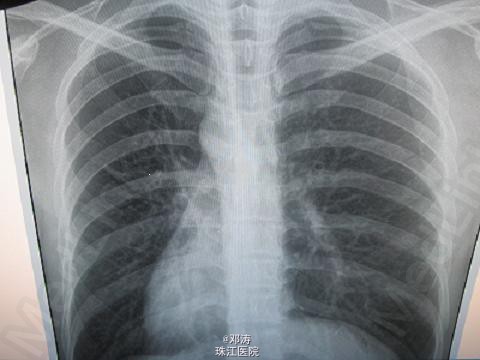

T37.5℃,P150次/分,R65次/分,BP80/50mmHg,一般状况尚可,妊娠足月儿外貌,发育良好,哭声响亮,呼吸急促,伴口吐白沫,无鼻翼煽动及三凹征,口唇无发绀,皮肤红润,前囟平坦2.0cm×2.0cm,无波动感,球结膜无水肿,双瞳孔等大等圆,对光反应正常。双肺闻及少许中小水泡音,P150次/分,节律齐,心音有力,各瓣膜未闻及杂音。腹平软,肝脾未触及,肠鸣音3次/分,四肢肌张力正常,觅食反射、吸允反射、拥抱反射存在。 白细胞计数14.6×109/L,中性粒细胞0.64,红细胞计数4.02×1012/L,血红蛋白153g/L,血小板计数218×109/L。胸部X线片示双肺纹理增强。

患儿入院第8天,停用机械通气,第9天停用经鼻呼气末正压辅助通气。第10天患儿呼吸状况好转,无呻吟及口吐白沫,进乳良好,心脏杂音消失,体重无明显减轻,胸部X线片较前明显好转。出院后每个月随访1次,监测肺功能及神经系统及生长发育情况。